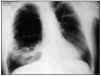

Varón de 60 años, diabético y con insuficiencia respiratoria crónica por enfisema pulmonar que ingresa por una neumonía en el lóbulo medio derecho. Se inició tratamiento con broncodilatadores inhalados, una cefalosporina de tercera generación y un macrólido, con mejoría inicial. En la tercera semana, ante la persistencia de cuadro febril, se realizó una radiografía de tórax (fig. 1) en la que se observa un infiltrado en el pulmón derecho de gran tamaño y con nivel hidroaéreo, por lo que se le añadió un antibiótico anaerobicida. En una TC torácica se observaba la lesión ya conocida (fig. 2. flecha izquierda) y otra pequeña imagen redondeada, con nivel hidroaéreo en su interior, en el espacio prevascular (fig. 2. flecha derecha). El fluido contenido en la lesión mayor era más denso que el agua y tenía burbujas de gas en su interior (fig. 2 punta de flecha). En un cultivo de esputo se cultivó Pseudomonas aeruginosa multisensible. Tras un acceso de tos, en una nueva radiografía de tórax (fig. 3) desaparece el infiltrado derecho, diseminándose la infección pulmonar, falleciendo el paciente días después en situación de shock séptico. Se estableció el siguiente diagnóstico: bullas pulmonares infectadas; bronconeumonía bilateral por P. aeruginosa.

Fig. 3.